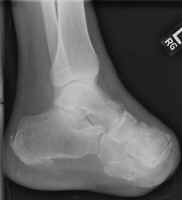

Amputations proximal to the transmetatarsal level often result in considerable gait

problems during walking. This is secondary to the loss of support and push-off.

When performed (often for the diabetic patient and in certain traumas), recent

improvements in preoperative testing (e.g. ultrasound) allow for a relative high accuracy

in predicting which patients will heal. The principle complication of the Lisfranc

amputation is a tendency towards an equinus deformity from the loss of dorsiflexor

attachments. If severe, such a deformity may require repeat amputation at a higher

level.